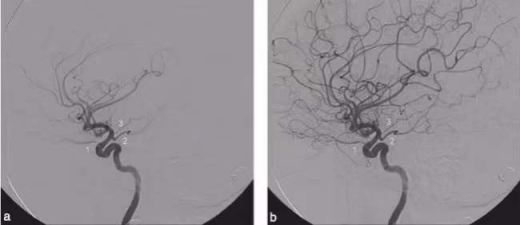

脑血管造影图

脑血管造影后可以帮助医生准确地了解血管病变的数目、位置、大小、形态、与周围血管的关系,医生可初步预测、了解疾病的发展、出血的风险、梗塞的风险等,从而判断是否需要进行干预、怎么干预等等。